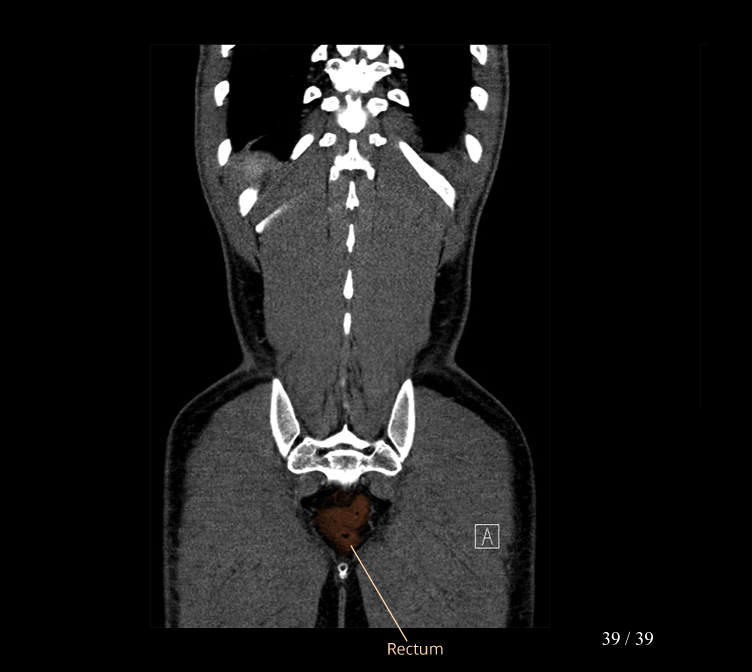

Body

Covers abdominal CT anatomy.